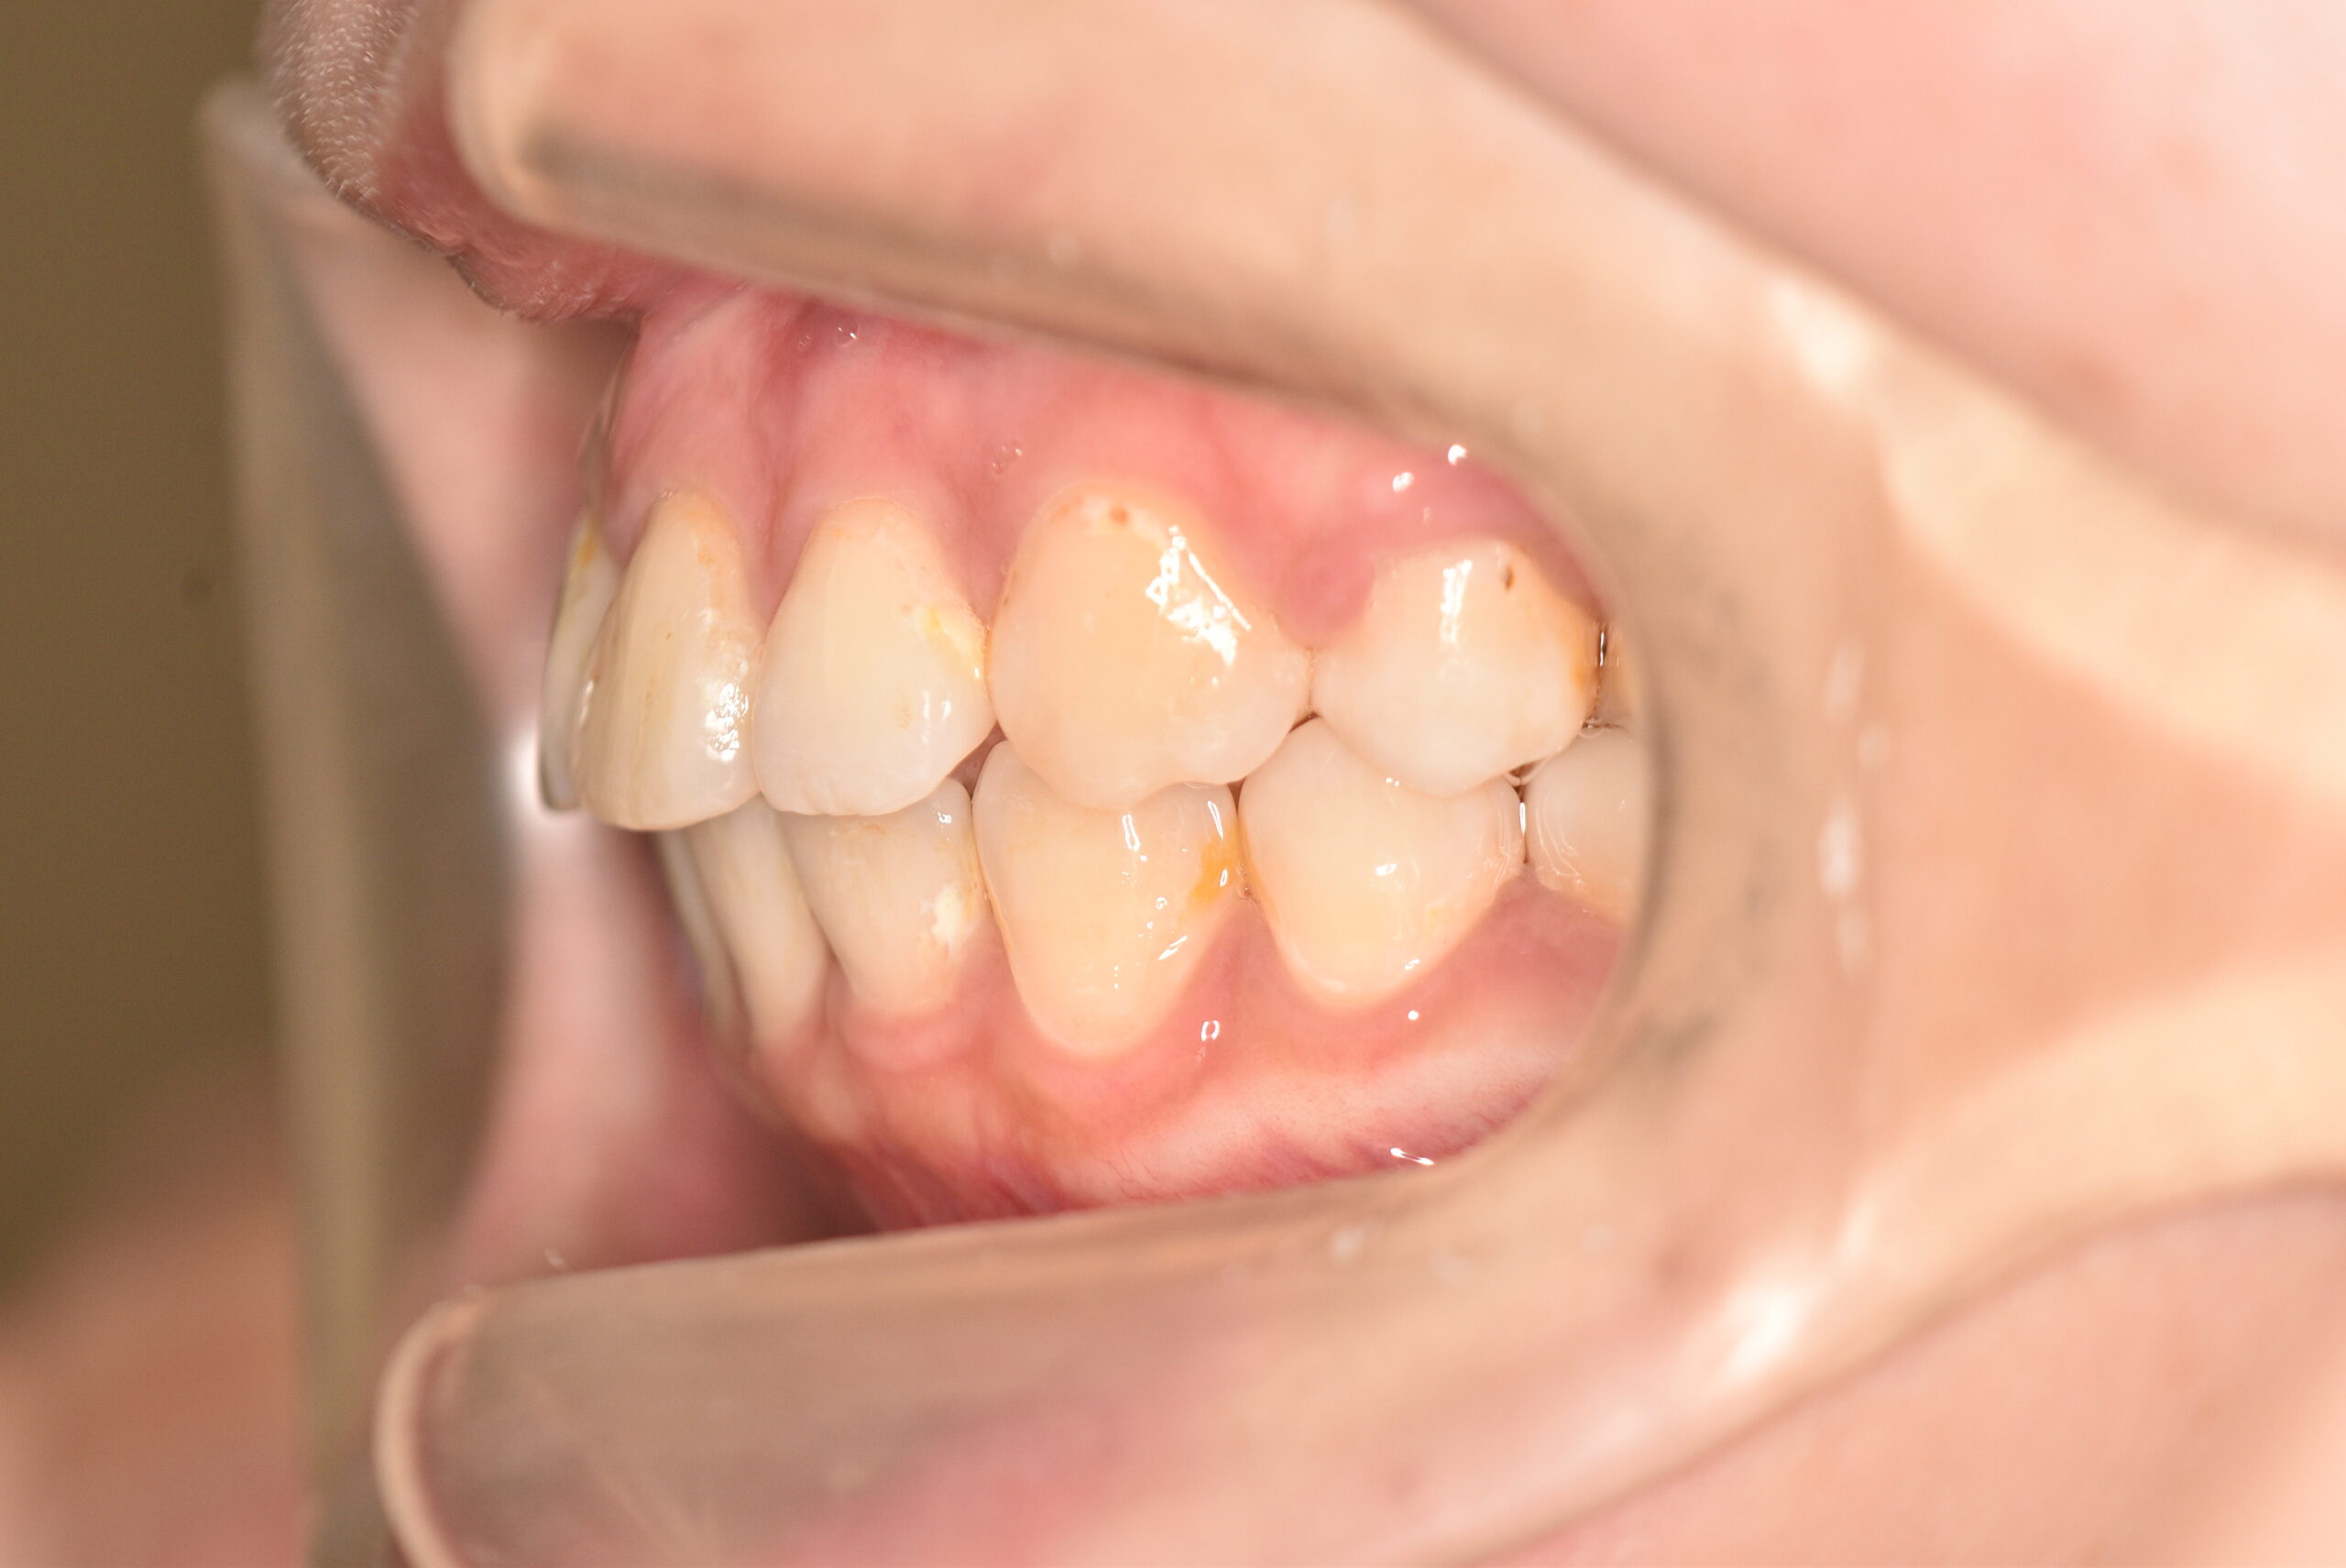

| 治療内容の詳細 | 初診時29歳の女性で、出っ歯を気にされ来院されました。 検査の結果、上顎前突を伴うアングルⅡ級1類不正咬合と診断しました。 治療としては、上顎左右第1小臼歯および下顎左右第2小臼歯をして、セルフライゲーションブラケット装置(デーモンシステム)で歯の配列を行いました。 同時に顎間ゴムにて咬合関係の改善を行いました。 この際、上顎に歯科矯正用アンカースクリューを設置し上顎前歯部後退時の土台としました。 治療期間は、2年6ヶ月でした。 |